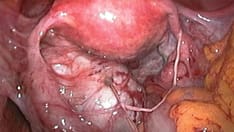

In patients with refractory symptoms, a multidisciplinary approach may be indicated. Patients with pelvic pain do not routinely need consultation with a gynecologist in the ED, though they should be directed to follow up on an outpatient basis. Exceptions include certain infectious entities (eg, abscesses), as well as endometriosis.

Treatment of secondary dysmenorrhea involves correction of the underlying organic cause. Specific measures (medical or surgical) may be required to treat pelvic pathologic conditions (eg, endometriosis) and to ameliorate the associated dysmenorrhea. Periodic use of analgesic agents as adjunctive therapy may be beneficial.